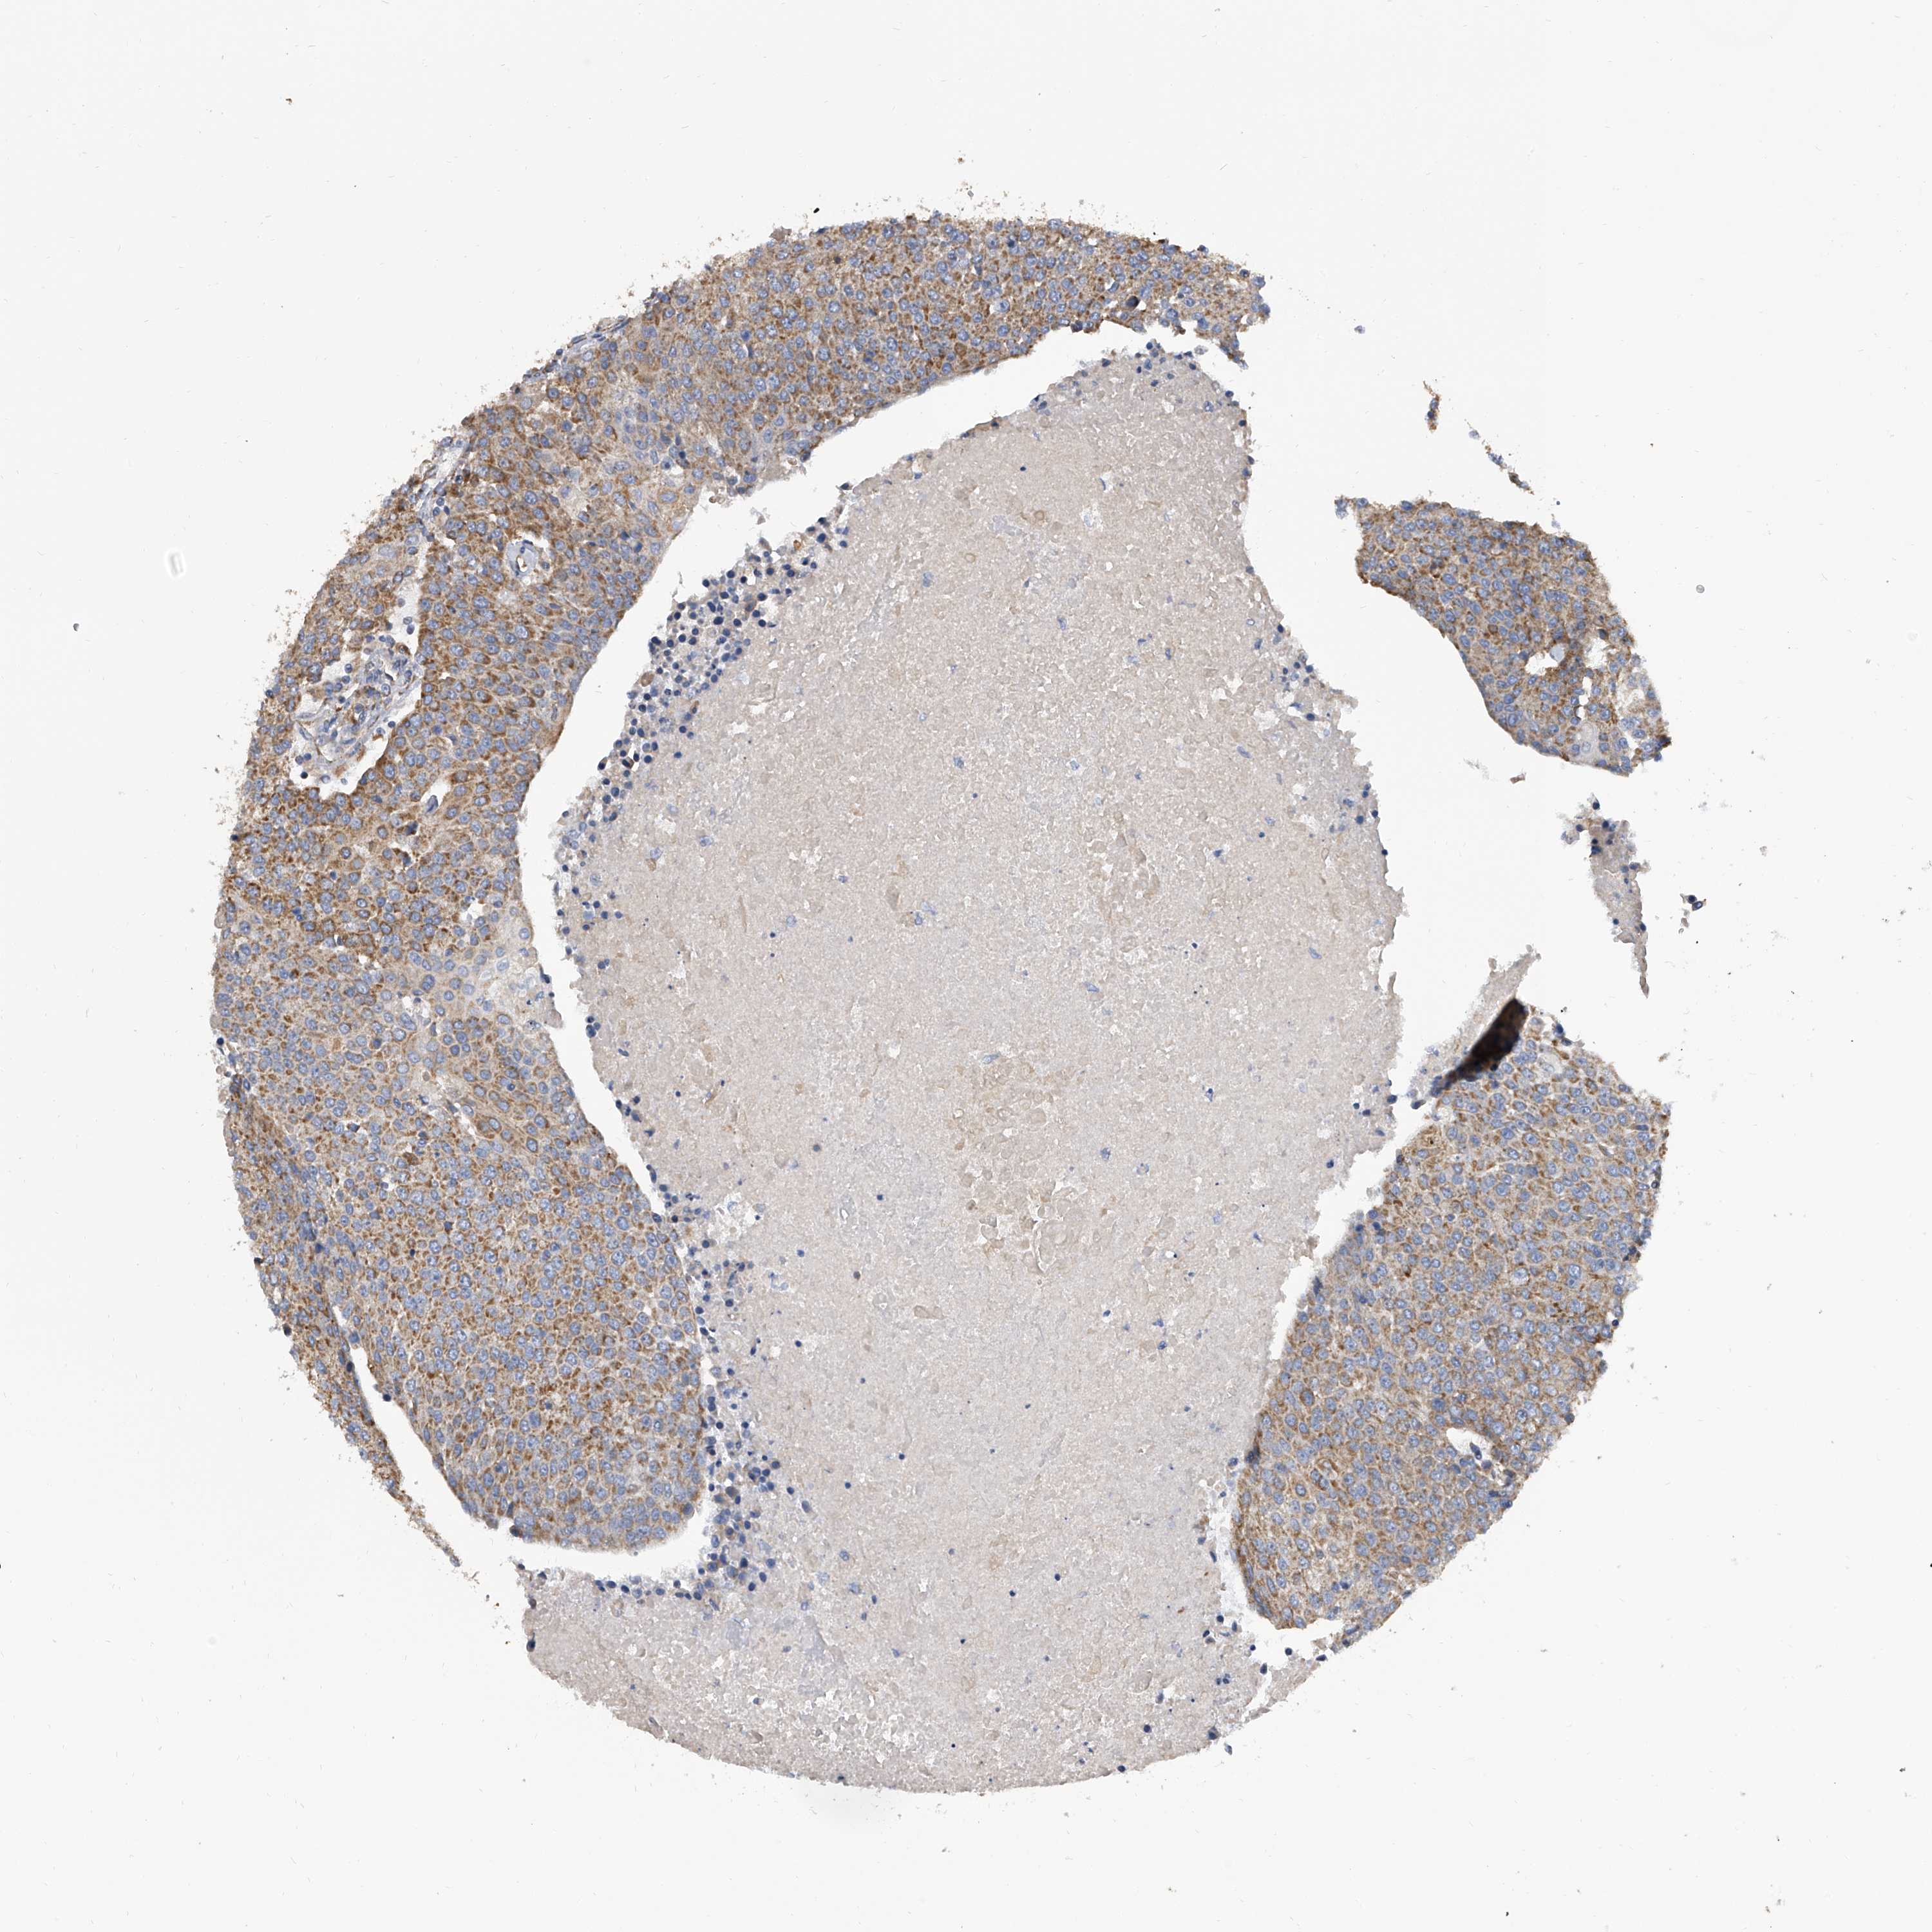

UROTHELIAL CANCER - Protein expressioni

A mouse-over function shows sample information and annotation data. Click on an image to view it in a full screen mode. Samples can be filtered based on level of antibody staining by selecting one or several of the following categories: high, medium, low and not detected. The assay and annotation is described here.

Note that samples used for immunohistochemistry by the Human Protein Atlas do not correspond to samples in the TCGA dataset.

Antibody stainingi

Antibody staining in the annotated cell types in the current human tissue is reported as not detected, low, medium, or high, based on conventional immunohistochemistry profiling in selected tissues. This score is based on the combination of the staining intensity and fraction of stained cells.

Each image is clickable and will lead to virtual microscopy that enables deeper exploration of all samples and also displays staining intensity scores, fraction scores and subcellular localization as well as patient and tissue information for each sample.

Antibody HPA030594

Antibody HPA055589

Antibody CAB033542

Urothelial carcinoma, Low grade

Urothelial carcinoma, High grade

Urothelial carcinoma, NOS